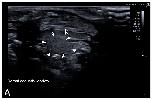

Figure 7. Representative HR-US images of Kaloula pulchra (A) and Xenopus laevis (B) males obtained in the longitudinal plane using a dorsal acoustic window. The testes (delimited by arrows) appeared as structures with oval morphology, mid echogenicity and homogenous echotexture. Testes were located just ventral or ventrolateral of the ipsilateral kidney (k). |